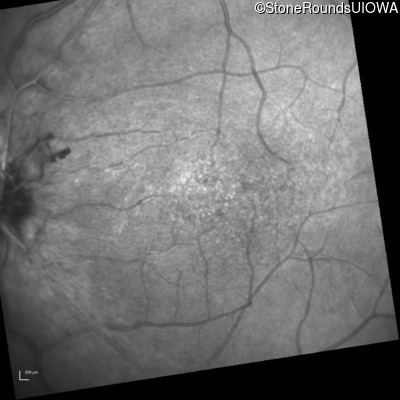

Infrared Fundus Photograph - Right - 20/30 -2

Exemplar

Infrared Fundus Photograph - Left - 20/50 -3